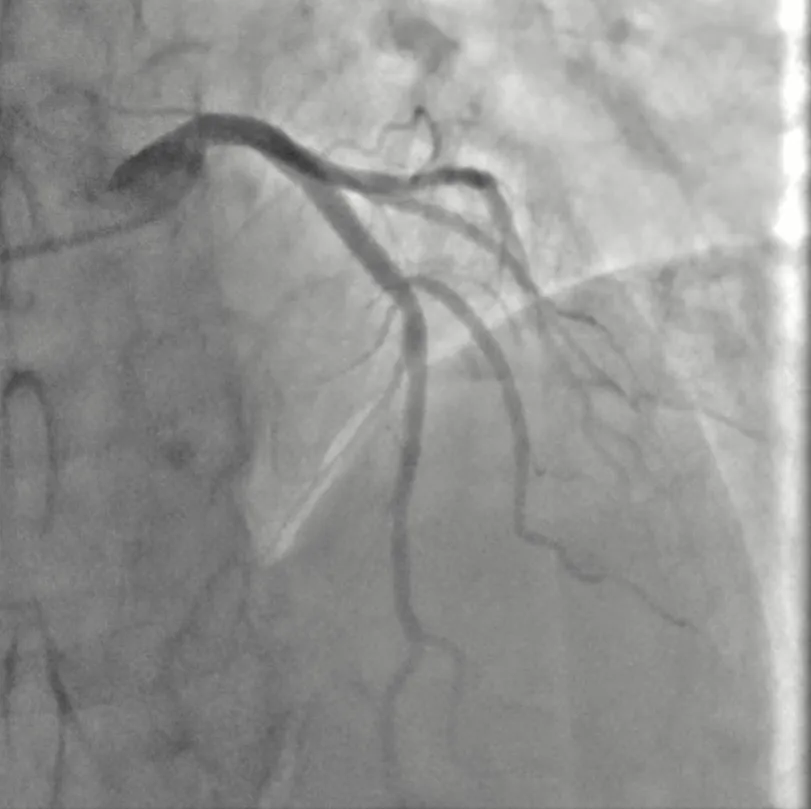

然而,造影结果却出人意料:冉先生的冠状动脉各主要分支均未见明显狭窄或阻塞。症状与影像结果不符,诊断陷入僵局。结合患者“静息时发作、硝酸甘油可迅速缓解”的典型特征,心血管内科专家团队高度怀疑其病因为冠状动脉痉挛。为了获得确凿证据,经与患者及家属充分沟通,团队决定在导管室内为其实施麦角新碱冠脉激发试验。

试验过程严谨有序:在持续心电、血压监测下,医生经导管向左冠状动脉内缓慢推注麦角新碱。药物推注后约1分钟,患者立即再现了与入院时相同的胸痛,与此同时,监护心电图再次显示前壁导联ST段改变。冠脉造影实时影像清晰地显示:患者的前降支冠状动脉出现严重的弥漫性痉挛,管腔直径狭窄超过90%,几近闭塞(右冠状动脉激发试验阴性)。“罪魁祸首”在镜头下原形毕露!团队立即经冠脉注入硝酸甘油,痉挛迅速解除,血管恢复通畅,患者胸痛随之消失,心电图也恢复正常。

至此,一例典型的“变异型心绞痛”(冠状动脉痉挛所致)被明确诊断。从“无异常”到“重度痉挛”,动态的造影影像和心电图变化构成了诊断的铁证。

图:冠脉造影基础状态